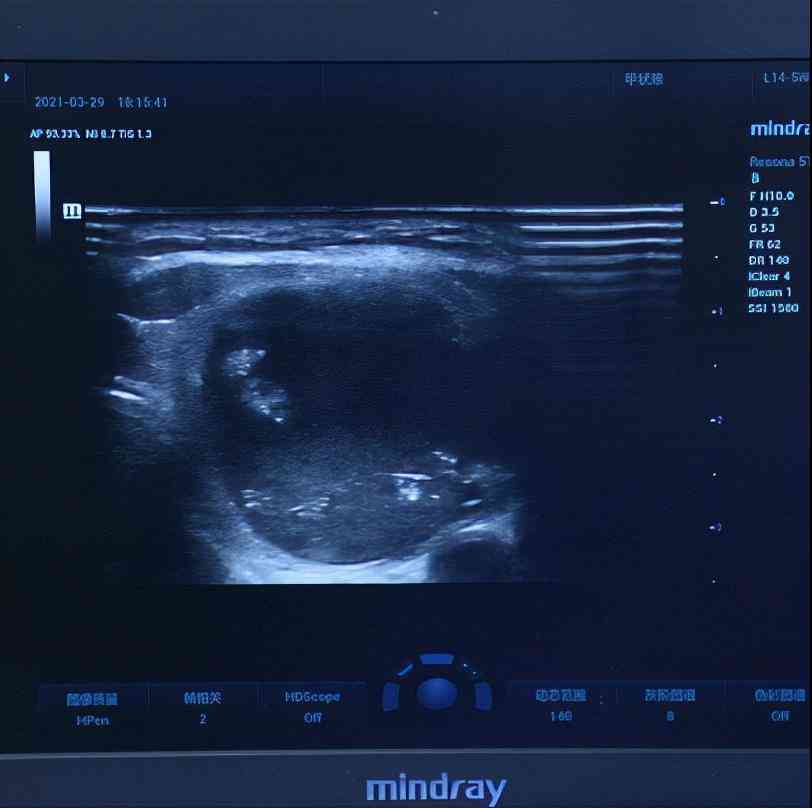

四維彩超出來,發(fā)現(xiàn)葛女士還有3mm的一個小結(jié)節(jié),這個結(jié)節(jié)的評分很低,良性的可能性很大,我跟她說如果不想做手術(shù)可以先觀察,等長大一點(diǎn)了做微創(chuàng)消融術(shù)也是可以的。